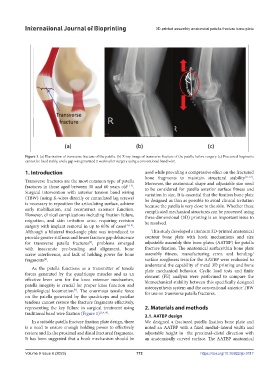

Figure 1. (a) Illustration of transverse fracture of the patella. (b) X-ray image of transverse fracture of the patella before surgery. (c) Fractured fragments

cannot be fixed stably, and a gap was generated 2 weeks after surgery using a conventional band wire.

traditional band wire fixation (Figure 1) [3,4,10] .